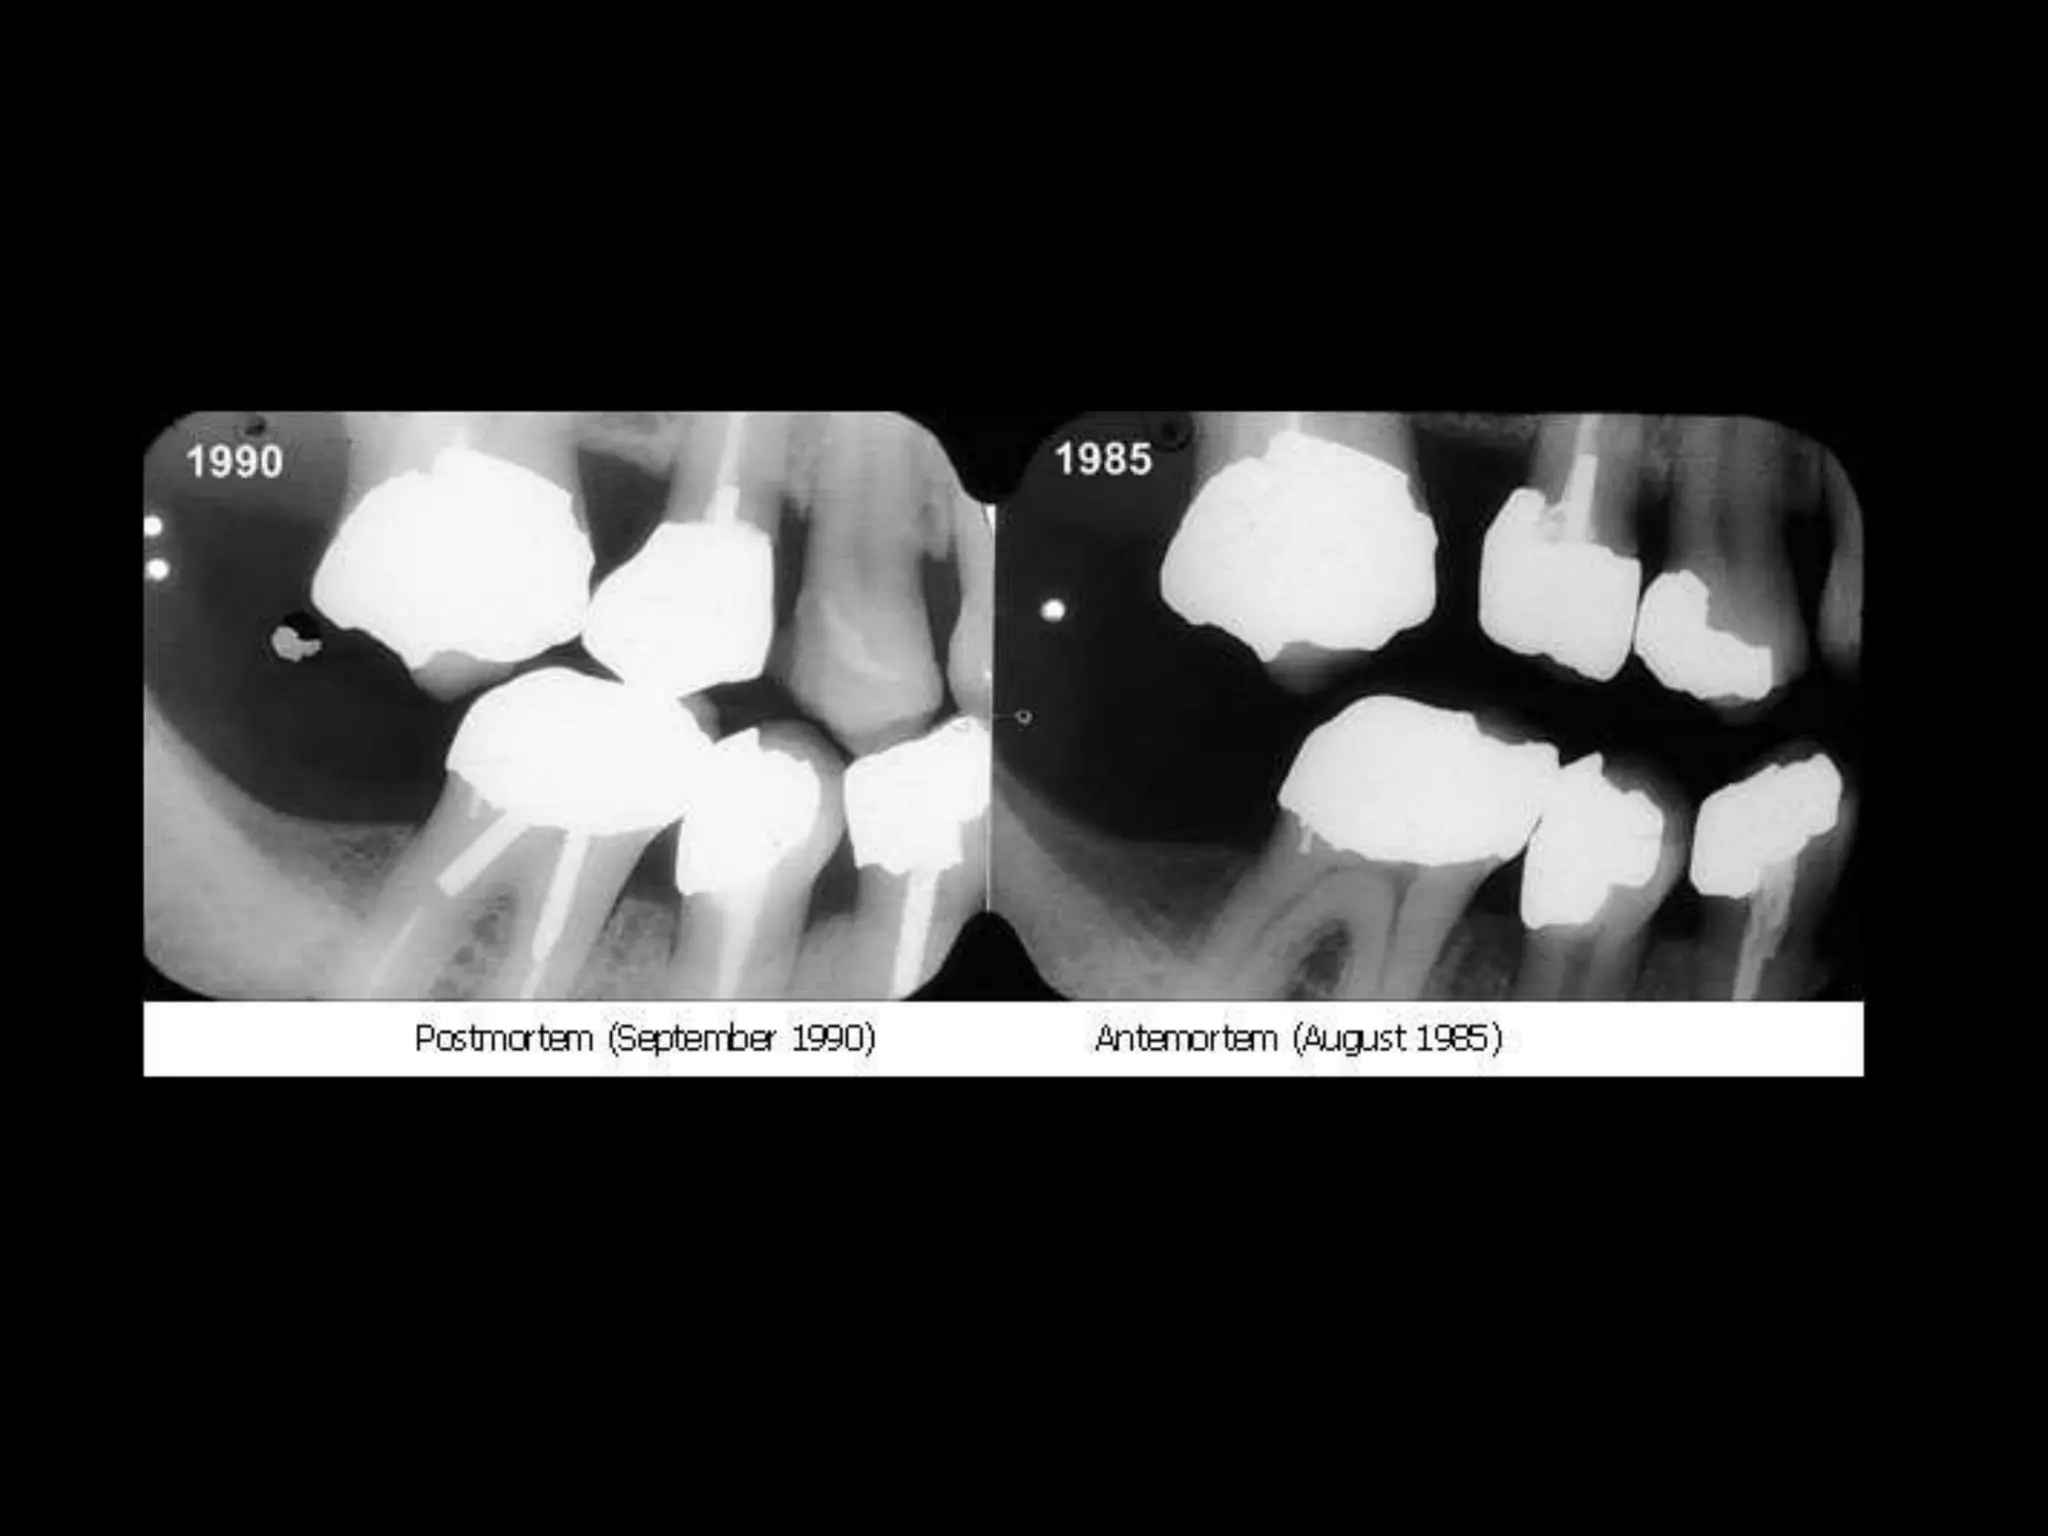

C. COMPARING POST – AND ANTE-MORTEM

DENTAL RECORDS

– Compared by written notes, Study casts, radiographs,

Photographs etc.,

– Radiographic identification is often conclusive.

2. Restorations & Prosthesis – Tooth no., surfaces

involved, dental materials used - type of material, no.

of replaced teeth.

6. Root canal therapy – Type of filling material used,

imperfections of the canal